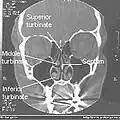

Coronal section of nasal cavities -